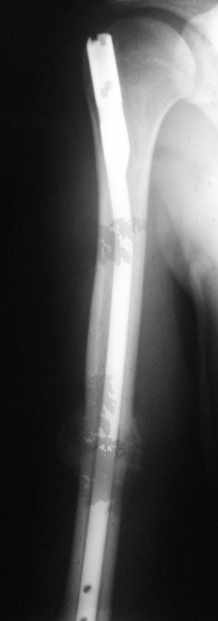

Блокируемый незаблокированный штифт.

Уважаемые коллеги!Обратился пациент, оперирован не у нас.

Что делать?

Варианты:

1. Заблокировать.

2. Ничего не делать.

3. Заменить штифт на более толстый.

4. Еще варианты?

однозначно не блокировать и не убирать - есть прекрасная мозоль и все отлично срастается. Мне плохо видно - выступает ли гвоздь проксимально ( кажется, нет, гвоздь строго в уровень с костью)?

Если гвоздь хоть чуть-чуть выступает - убрать гвоздь как можно скорее (месяца через 3 после травмы), если не выступает - оставить все как есть

Спасибо. А не слишком ли хороша мозоль?

Большая мозоль - здоровый организм УСПЕШНО компенсирует недостатки фиксации.

Раз есть боль в области плеча - скорее всего, таки травмируется ротаторная манжета плеча гвоздем - либо подождать еще месяцок и гвоздь убрать, пока он больному не разорвал манжету "в клочья", либо (в идеале, если есть желание, операционное время, инструмент того же производителя, которым пользовались в Склифе, понимание со стороны больного и т.д) - забить гвоздь на полсантиметра глубже и заблокировать одним проксимальным шурупом, чтоб предотвратить его миграцию в канале

Само же состояние перелома мне не внушает никаких сомнений или опасений

Гвоздь для плеча - дело не очень хорошее, и, честно говоря, на этих снимках показаний к такому методу лечения я никаких не вижу. Больше процент несращений, часто (до 20-30 процентов) встречаются осложнения со стороны плечевого сустава... Однако, это уже выходит за пределы обсуждаемой темы

Пациент обратился с жалобой на лигатурный свищ.

Амплитуда движений 70-80% от контрлаптеральной конечности с умеренной болью в месте перелома. Наиболее болезненно - заведение руки за спину (появляется боль в области плечевого сустава). Отведение - градусов 70, далее за счет лопатки.

Обычное дело, пусть разрабатывает давно, лучше с методистом. Тут по снимкам проблем не видно. Винты вводить необязательно - если хирург знает, что делает. Например, если получился хороший press-fit из-за несоответствия формы гвоздя и канала.